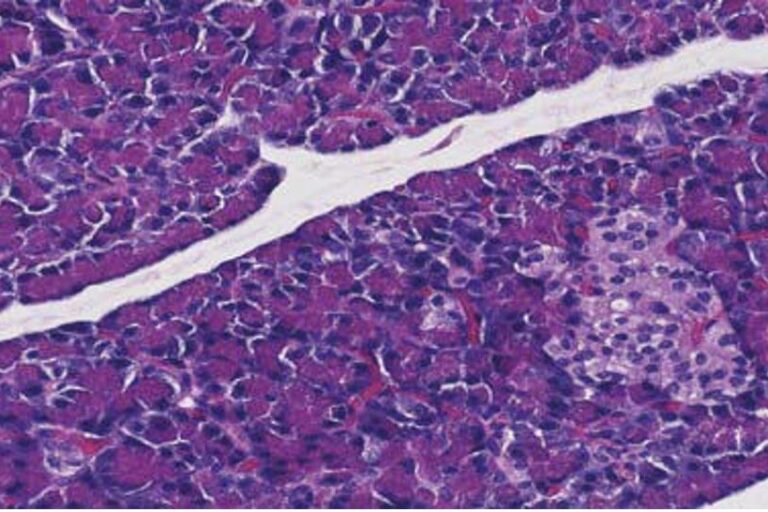

Patologia

Aggiornamenti LABOKLIN 201622. Maggio 2016

L’esame microscopico di sezioni di tessuto dopo fissazione in formalina (10%) e inclusione in paraffina,…